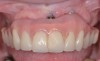

After implant surface decontamination, the specific surgical approach (eg, access surgery, respective, or regenerative) for each case is heavily dependent on the position of the implant in the oral cavity, as well as the configuration of the peri-implant defect (Figure 7).24 In a recent meta-analysis, an average 2 mm to 3 mm peri-implant probing depth reduction was achieved following surgical intervention.25 Also, implant surface modification (implantoplasty) (Figure 8) was superior to access flap alone. The addition of bone grafts yielded an average of 2 mm of bone fill in defects treated with a regenerative approach. Regenerative treatments may be contraindicated in smokers.

Fig 7. Access flap surgery was performed to assess the defect.

Figure 7

Fig 8. Ostectomy was performed with implant surface modification.

Figure 8